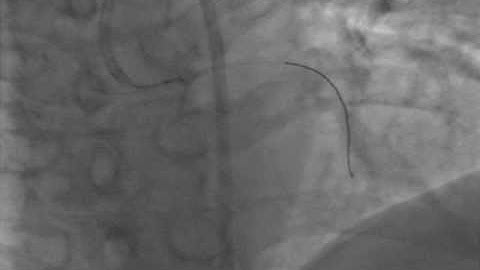

AndraTec Exeter Snare Intravascular Retrieval and Techniques in foreign body retrieval